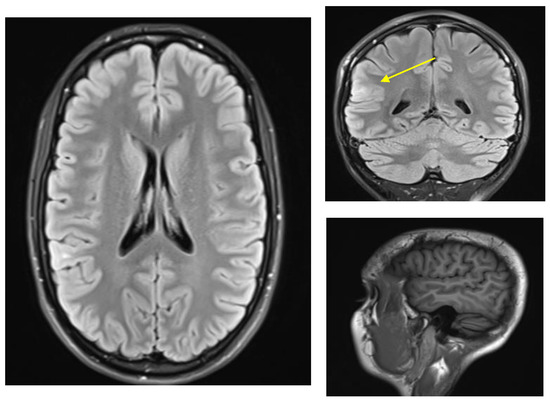

The patient was seen at our center at age 24. An EEG showed right posterior temporal polyspike discharges and sharp waves during wakefulness and sleep. An MRI head scan showed a focus of T2 signal abnormality involving the subcortical white matter of the right superior temporal gyrus posteriorly suggestive of focal cortical dysplasia (Figure 1). At that time, she was started on levetiracetam and eventually reached a dose of a 1000 mg b.i.d. while tapering off the oxcarbazepine. She was also started on clonazepam as needed for anxiety. She thought that the levetiracetam worsened her anxiety and she also had more frequent auras consisting of a feeling that her brain was “scrambled”. She therefore stopped the levetiracetam after a month and restarted oxcarbazepine 600 mg b.i.d. Soon after that, she was started on lamotrigine with the dose gradually increased to 100 mg b.i.d. Within a few weeks, she developed red spots on her hands and fingers, but this was not thought to be an allergic reaction. She was slowly tapered off oxcarbazepine over 2 months, at which time the red spots resolved. Given that the patient was on lamotrigine in the past, it was thought these spots were not related to lamotrigine. At age 25, the patient’s dose of lamotrigine was increased to 250 mg b.i.d. and later to 250 + 300 mg per day; however, she continued to have seizures (same as prior with staring +/− loss of awareness +/− epigastric sensation), and she also had side effects of diplopia and dizziness. Specifically, the patient stated she saw double when looking at objects in near and far distance, and this could be horizontal or vertical stacking. When she would close one eye, the double vision and the dizziness would resolve. For this reason, she was gradually tapered off lamotrigine and after that, she was on no antiepileptic medications and was having seizures up to three to four times per day.

Figure 1.

MRI-FLAIR findings of FCD in right posterior temporal-parietal-occipital junction. ((Left), axial, (right top) coronal, (right bottom) sagittal MPRAGE) Tiny focus of T2 signal abnormality involving the subcortical white matter of right superior temporal gyrus posteriorly (yellow arrow). Findings of this sort are suggestive of focal cortical dysplasia [11].